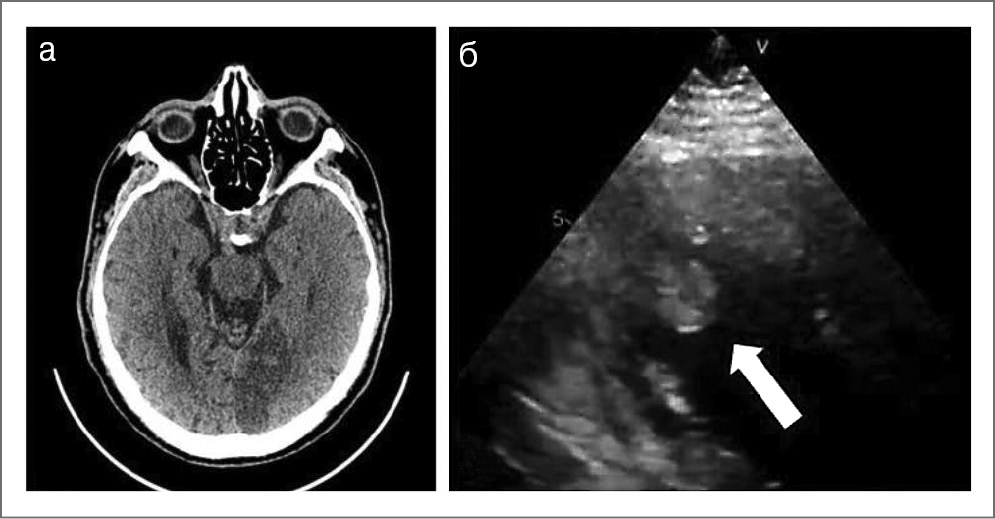

Тромб в ЛЖ. Формирование тромба наблюдается у 15% пациентов с ИМ в области передней стенки, у 40% пациентов с передним ИМ и снижением ФВ менее 40% [12] и пятикратно повышает риск системной эмболии [13]. Кардиоэмболический инсульт развивается у 12% пациентов с тромбозом ЛЖ вследствие ИМ в среднем через 21 день после выявления тромба. Независимыми предикторами ИИ выступают протрузия тромба, неэффективность его первоначального растворения и рецидив тромбоза [14].

Рис. 2. Клинический пример. Мужчина 47 лет перенес ИИ в бассейне левой задней мозговой артерии: а – КТ головного мозга; б – гипокинез ЛЖ со снижением ФВ на ЭхоКГ (32%) и мобильный тромб в области верхушки (белая стрелка указывает на тромб).